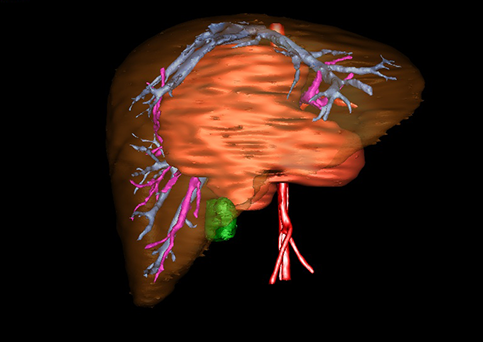

近年来由于数字医学的发展,基于可视化三维重建技术的计算机辅助手术系统极大推进了小儿肝脏肿瘤的精准手术的进步。可以立体透视肝脏解剖、精确掌握肝段的边界、精确测算肝段乃至任意血管所支配的功能体积、准确定位病灶及其与邻近血管的解剖关系,最终对不同手术方案进行比较、筛选和优化。因此,计算机辅助手术规划系统是实现精准肝切除的有力辅助工具,是未来数字外科、精准外科等21世纪外科新理念的重要技术支撑。

计算机辅助手术规划系统具有良好的操作可行性、计算准确性和三维显示效果,可半透明、交互式显示真实的肝内立体解剖关系和空间管道变异,准确计算肝内管道的直径、走行角度,两点间的垂直距离,和任意血管的支配或引流范围等传统二维影像无法获取的信息,有助于实施个体化手术,提高了手术的确定性、预见性和可控性。计算机辅助手术规划系统可直观显示预留肝脏的结构和功能,并可通过虚拟切割功能辅助术者对手术方案进行蹄选和优化,系统评估手术风险和制定对策,改变了部分二维规划的术式和切除范围,使部分二维规划认为不能切除的患者成功手术,提高了手术的根治性、安全性和病变的可切除性,更加符合精准肝脏外科的术前规划要求。详见第11章。

随着计算机技术及影像检查技术的不断发展,以精确的术前影像学和功能评估、精细的手术操作为核心的精准肝切除技术日益受到重视。基于数字医学的计算机辅助手术技术(computer-assisted surgery,CAS)则是实现肝脏精准手术操作的基础。计算机辅助手术系统(CAS)可将术前二维(two dimensional,2D)的CT/MRI影像数据进行三维(three dimensional,3D)重建,建立个体化的肝脏三维解剖模型,清晰显示肝脏内脉管系统的走行及解剖关系,还原病灶与其周围脉管结构的立体解剖构象,准确地对病变进行定位、定性和评估,制定合理、定量的手术方案,实施个体化的肝脏血管取舍分配方案及实施精准肝脏手术。一般认为CAS包括:创建虚拟的患者的图像;患者图像的分析与深度处理;诊断、手术前规划、手术步骤的模拟;术中实时导航。应用本技术后,由于可以更清晰地看出肿瘤的界限,特别是根据肝血管的显影,判断出肿瘤与门静脉及肝静脉的关系以在手术前较准确地估计出手术成功切除的可行性。以往部分根据普通强化CT判断无法手术的病例而被评估为可以成功切除并手术成功。